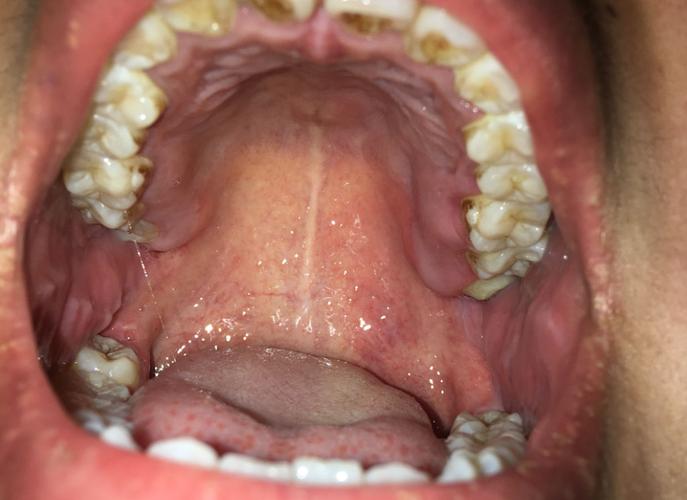

口腔上颚中间白线是啥?正常吗? 口腔上颚中间白线的本质 您所说的“白线”,在医学上通常被称为腭中线或腭缝线,它并不是一个真正的“缝”,而是上颚(硬腭)左右两块骨头在胚胎发育时融合后留下的痕迹。(图片来源网络,侵删) 您可以把它想象成: 胎儿的“愈合线”:在胎儿时期,口腔的上半部分是由左右两部分逐渐向中间生长并最终融合在一起的,腭中...

宝宝口腔上颚白点是什么? 🧐 常见宝宝口腔上颚白点/白斑的可能原因及特征描述 🍼 1. 鹅口疮 (Thrush / 口腔念珠菌感染) 特征描述: 外观: 白色或乳黄色、略凸起的斑点或斑块,看起来像牛奶残渣或凝乳。 质地: 擦拭时不容易擦掉(与奶渍不同),如果用力擦拭,可能会留下红色、出血的创面。 分布: 最常见于上颚、颊内侧...